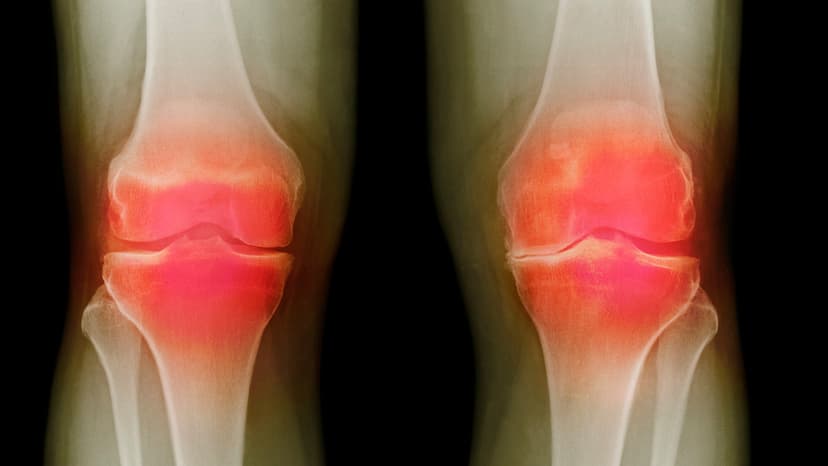

These advanced therapies aim to provide a cure for osteoarthritis, a condition affecting millions. Current treatments only manage symptoms, but these new methods focus on regenerating damaged joint tissues. Researchers believe these solutions could eventually be applied to any joint in the body.